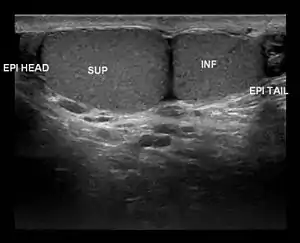

Ultrasound scan showing a side view of Type A3 polyorchidism, with annotations showing the superior and inferior testes and the head and tail of the epididymis

• Type A3: The supernumerary testicle shares the epididymis and the vas deferens of the other testicles.